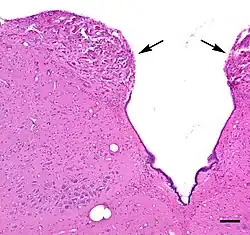

The area postrema is a paired protuberance found at the inferoposterior limit of the fourth ventricle.[1][5] Specialized ependymal cells are found within the area postrema. These cells differ slightly from the majority of ependymal cells (ependymocytes), forming a unicellular epithelial lining of the ventricles and central canal. The area postrema is separated from the vagal trigone by the funiculus separans, a thin semitransparent ridge.[1][5] The vagal trigone overlies the dorsal vagal nucleus and is situated on the caudal end of the rhomboid fossa or 'floor' of the fourth ventricle. The area postrema is situated just before the obex, the inferior apex of the caudal ventricular floor. Both the funiculus separans and area postrema have a similar thick ependyma-containing tanycyte covering. Ependyma and tanycytes can participate in the transport of neurochemicals into and out of the cerebrospinal fluid from its cells or adjacent neurons, glia or vessels. Ependyma and tanycytes may also participate in chemoreception.[1][5]